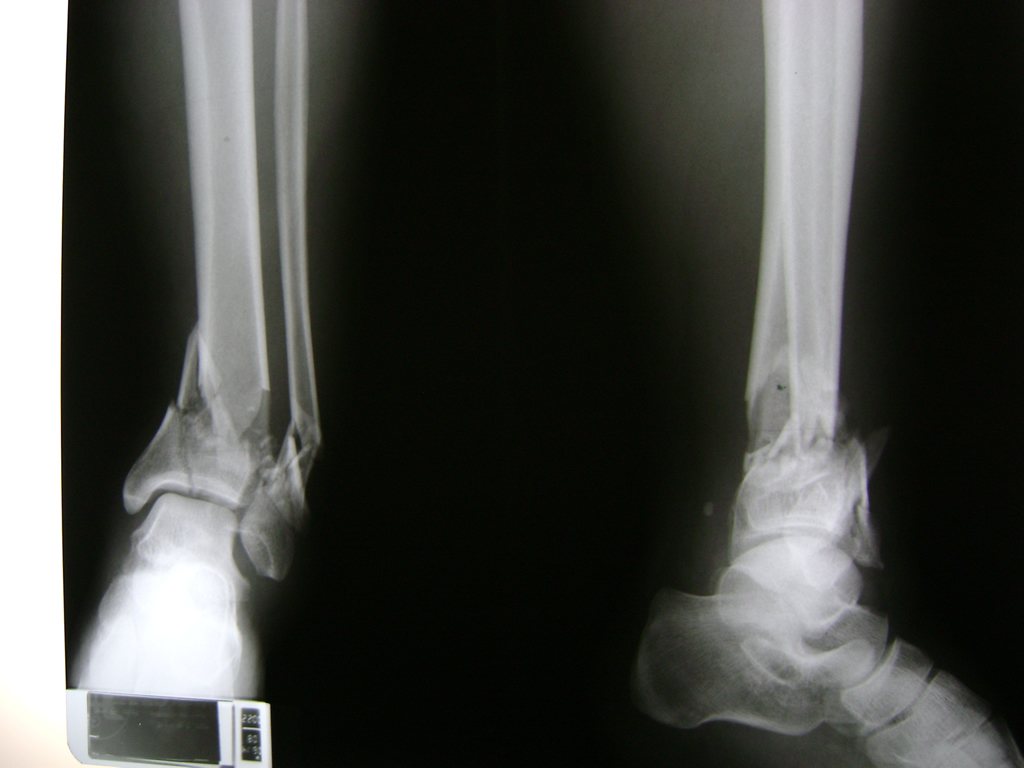

Una fractura de tobillo es la rotura de uno o más de los huesos del tobillo. Estas fracturas pueden ser:

- Parciales (el hueso está sólo parcialmente fisurado, no del todo).

- Completas (el hueso está perforado y está en 2 partes).

- Los extremos de los huesos están desalineados entre sí (desplazados).